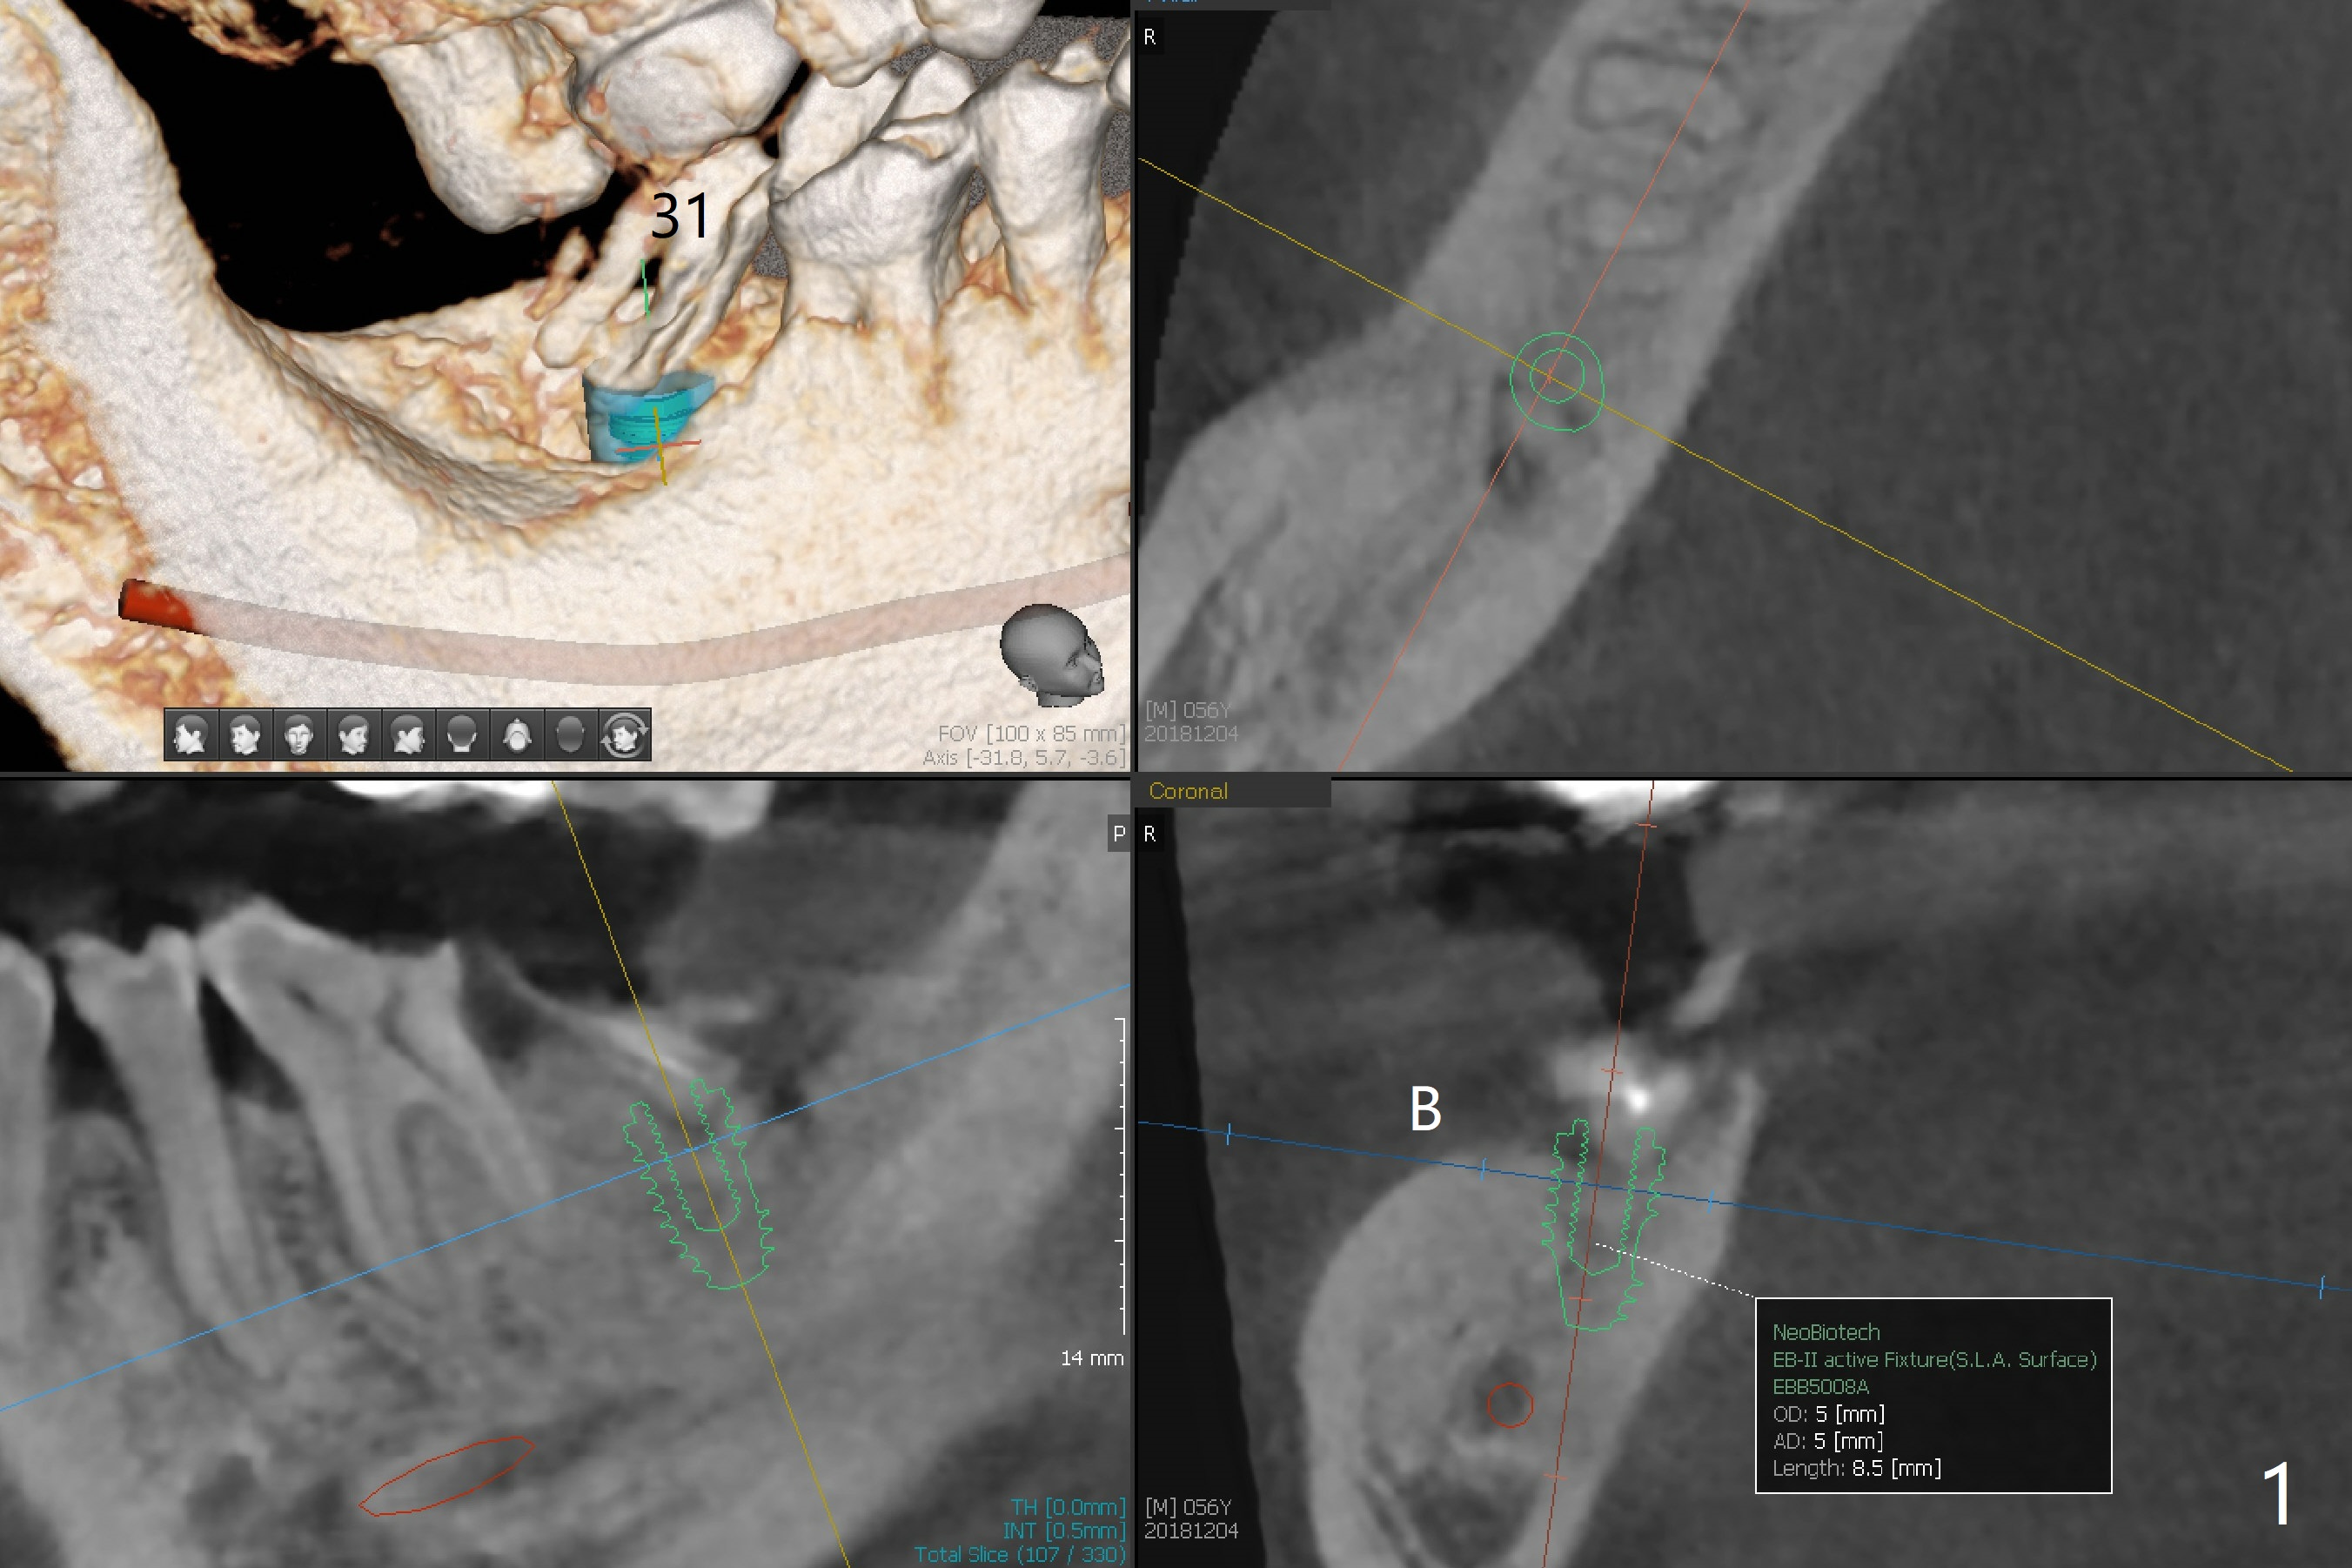

Dense Bone

A 56-year-old man agrees to have immediate implant at #31 (Fig.1-5) 2 year post (re)cementation at #14,15. Osteotomy should be gentle with copious irrigation because of dense bone (Fig.4). After implant osteointegration, a provisional will be fabricated to intrude the supraerupted tooth #2 (Fig.5).